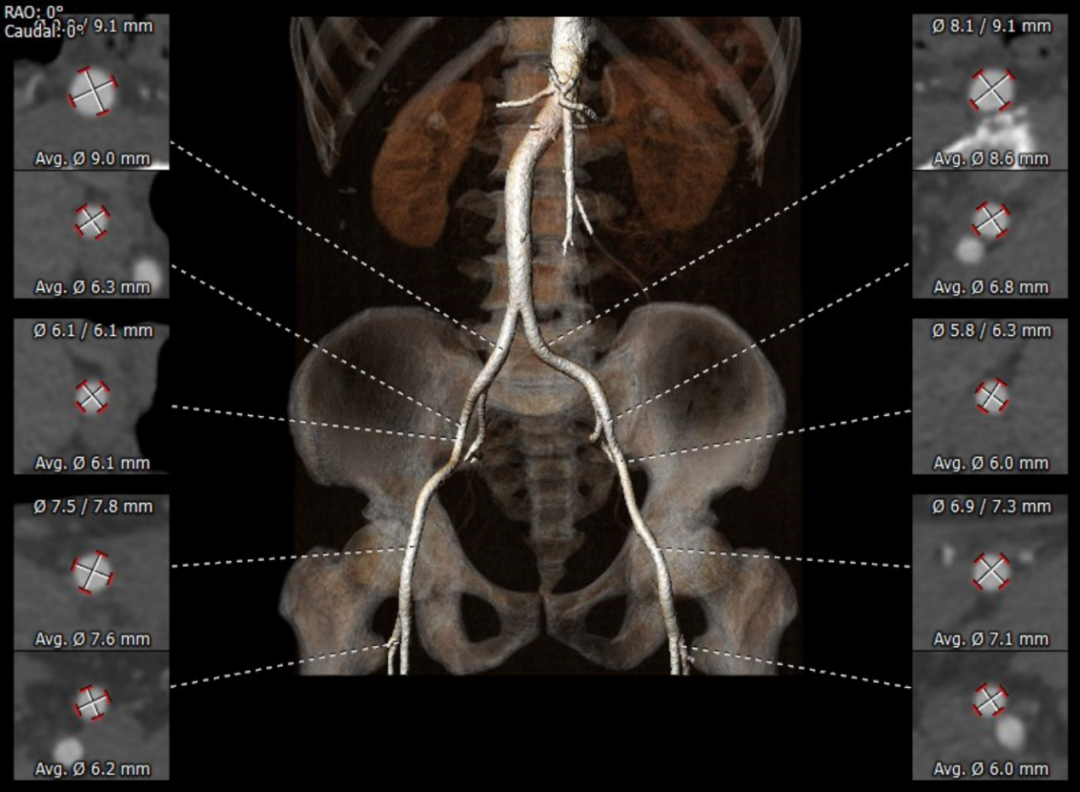

患者男性,70岁,重度钙化型主动脉瓣狭窄,STS评分8.6%,常规外科手术高风险。术前心脏超声提示主动脉瓣严重增厚钙化,峰值流速5.4m/s,平均跨瓣压差82mmHg。CT评估结果显示主动脉瓣重度钙化,瓣环平均直径23.9mm,瓣环面积448.4mm²。左冠脉开口高度8.5mm,右冠脉开口高度12.2mm。该患者左、右冠状动脉开口高度低,左冠瓣叶较长伴钙化,且瓦氏窦较小,窦管交界处高度低,冠状动脉阻塞风险高,手术操作复杂。

瓦氏窦直径

外周血管评估